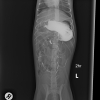

ديروز من بردمش دكتر و اونا نظرشون اين بود كه ممكنه چيزي قورت داده باشه و توي شكمش گير كرده باشه. سوفي xray شد و گفتند مقدار زيادي گاز توي شكمش هست، بهش berim contrast دادن و يكساعت بعد دوباره xray گرفتن و فقط مقدار كمي از كانترست خارج شده بود كه ميگفتن طبيعي نيست بايد خارج ميشده، صبح باز هم xray شد و بيشتر كانترست خارج شده بود ولي ميگفتن چون هنوز كمي اش مونده ممكنه چيزي باشه و بايد عمل بشه، اما من هنوز متقاعد نشدم، آيا واقعا اگه چيزي بود نبايد توي سه بار عكس گرفتن اونم بعد كانترست نباد نشون بده؟ سوفي بينهايت آب بدنش كم شده و واقعا نياز به سرم داره، ديگه بالا نياورده اما تا ديشب اسهال داشت. اونا بيست و چهار ساعت براي عكس نگهش داشتن تازه امروز گفتن بايد بيست و چهار ساعت ديگه بمونه براي سرم، اينجوري من فقط شارژ ميشم بدون اينكه مطمئن باشم قضيه چيه و اين كوچولوي زبون بسته هم هنوز حالش خوب نيست، من جواب ها رو براتون ايميل ميكنم، اگه نظرتون رو بگيد واقعا مديونتون ميشم.